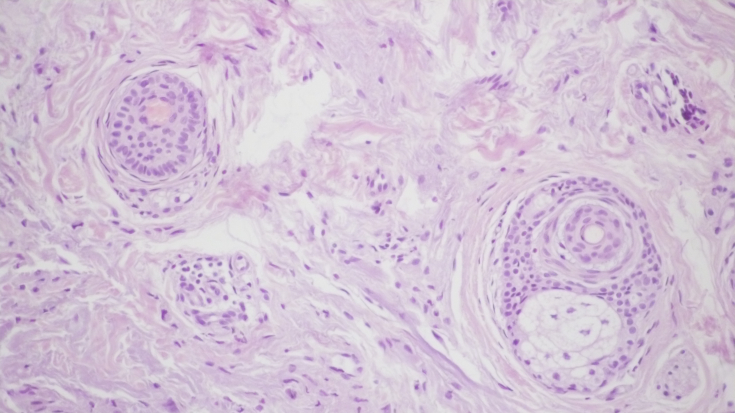

За даними інструментального дослідження, у комбінованій схемі апаратно-ін'єкційного ефекту зникла лімфоїдно-клітинна інфільтрація дерми, що свідчить про чітку синергію обраних методик у схемі комплексного anti-age рішення для вікової шкіри.

мал.5. Комбіноване введення пептидного препарату та радіохвильового впливу на шкіру. Відсутність лімфоїдно-клітинної інфільтрації дерми з очаговою проліферацією фібробластів, х200.